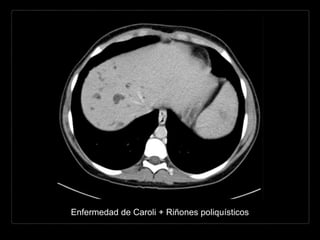

Enfermedad de Caroli + Riñones poliquísticos